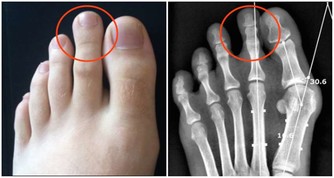

陳 昌平說明大腸癌的成因:「簡單說,是先有便祕,接著產生息肉,再病變成大腸癌。」大腸是由升結腸、橫結腸、降結腸及乙狀結腸等所構成,左側的大腸管徑比右 側大腸窄,當有腫瘤發生時,就會出現腸阻塞而引起便祕、腹脹甚至腹痛的情形。因為糞便大多在左側的結腸成形,因此如果阻塞的狀況嚴重的話,所排出的糞便就 會有時還會參雜血絲, 嚴重到便祕及解血便情形。